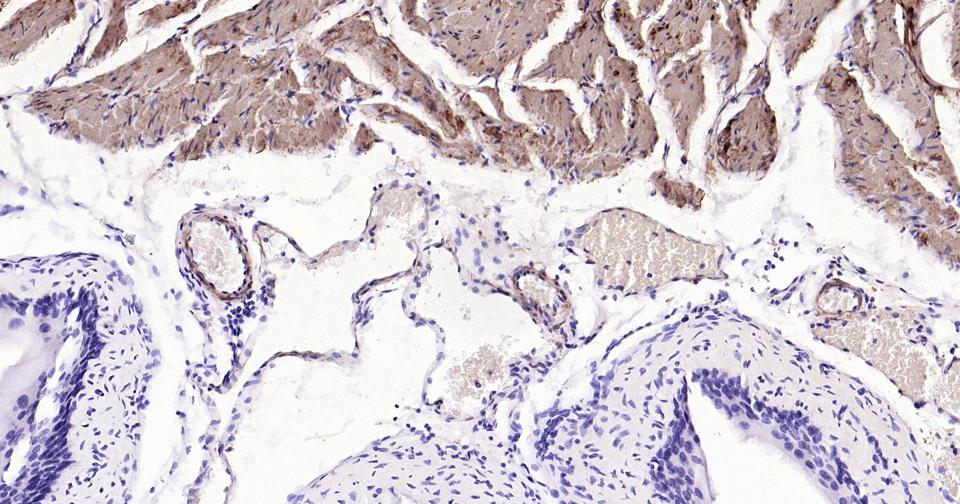

Paraformaldehyde-fixed, paraffin embedded Human Prostate; Antigen retrieval by boiling in sodium citrate buffer (pH6.0) for 15 min; Antibody incubation with CNN1 Monoclonal Antibody, Unconjugated(bsm-60845R) at 1:200 overnight at 4°C, followed by conjugation to the SP Kit (Rabbit, SP-0023) and DAB (C-0010) staining.

Paraformaldehyde-fixed, paraffin embedded Human Cervical Cancer; Antigen retrieval by boiling in sodium citrate buffer (pH6.0) for 15 min; Antibody incubation with CNN1 Monoclonal Antibody, Unconjugated(bsm-60845R) at 1:200 overnight at 4°C, followed by conjugation to the SP Kit (Rabbit, SP-0023) and DAB (C-0010) staining.

Paraformaldehyde-fixed, paraffin embedded Human Small Intestine; Antigen retrieval by boiling in sodium citrate buffer (pH6.0) for 15 min; Antibody incubation with CNN1 Monoclonal Antibody, Unconjugated(bsm-60845R) at 1:200 overnight at 4°C, followed by conjugation to the SP Kit (Rabbit, SP-0023) and DAB (C-0010) staining.